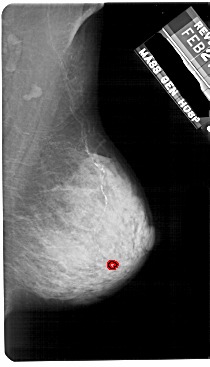

A_1753_1.RIGHT_CC

RIGHT_CC LINES 5491 PIXELS_PER_LINE 2956 BITS_PER_PIXEL 12 RESOLUTION 43.5 OVERLAY

FILE: A_1753_1.RIGHT_CC.OVERLAY

TOTAL_ABNORMALITIES 1

ABNORMALITY 1

LESION_TYPE CALCIFICATION TYPE PLEOMORPHIC DISTRIBUTION CLUSTERED

ASSESSMENT 4

SUBTLETY 1

PATHOLOGY BENIGN

TOTAL_OUTLINES 1

BOUNDARY